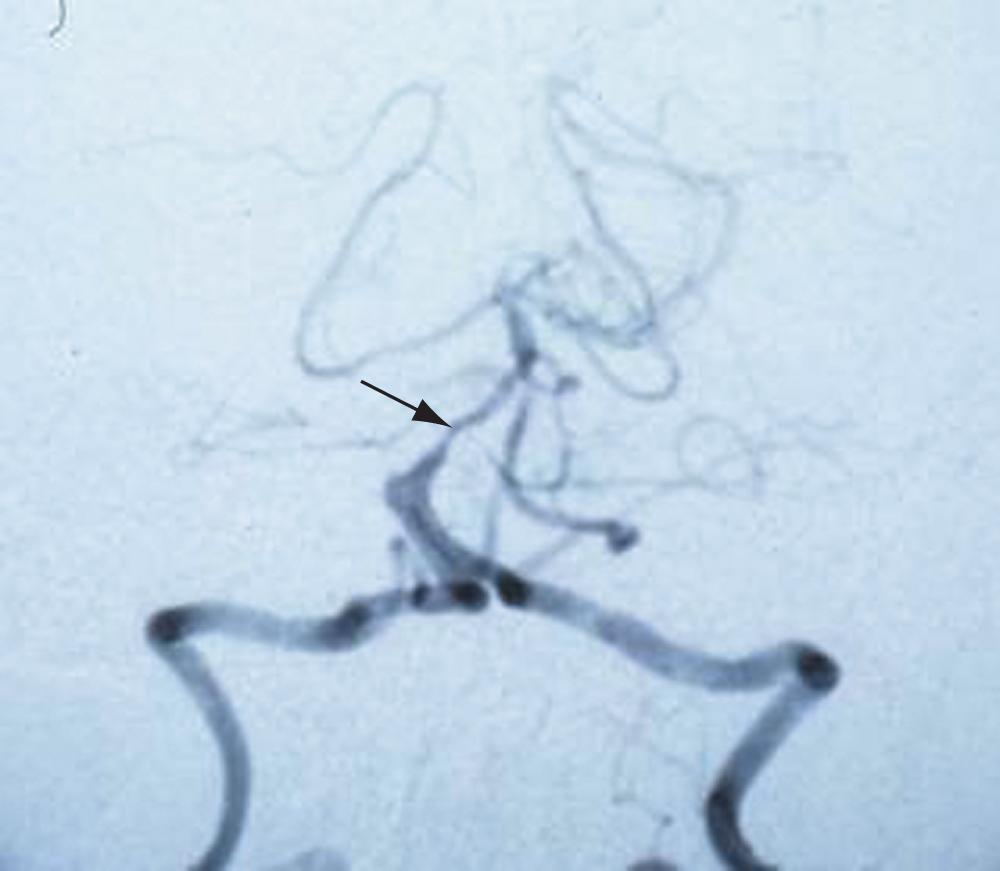

https://www.aao.org/image/vertebrobasilar-insufficiency Vertebrobasilar insufficiency. A 58-year-old woman had a sudden onset of diplopia and vertigo. Examination revealed a right third nerve palsy and ataxia. Symptoms and signs resolved over 24 hours. This cerebral angiogram showed marked stenosis of the basilar artery (arrow). (Courtesy of Karl C. Golnik, MD.)